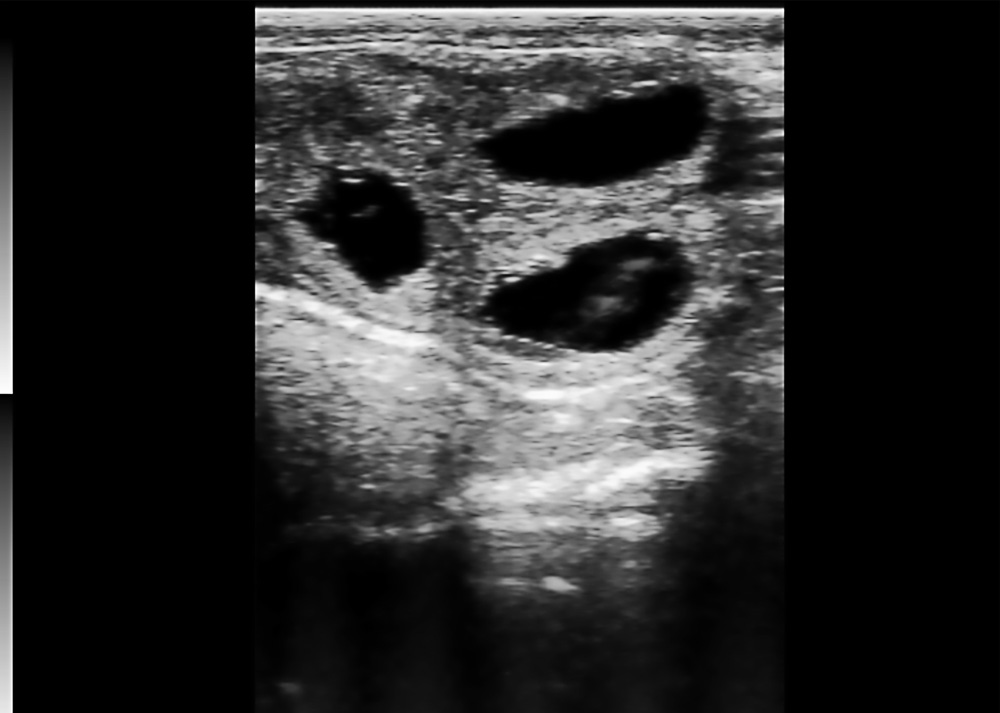

Ovarian Follicle Ultrasound

● Displays multiple follicle cavities of varied shapes.

● Layered echoes for structural recognition.

● Shows cavity distribution and size.

● For reproductive monitoring in livestock.